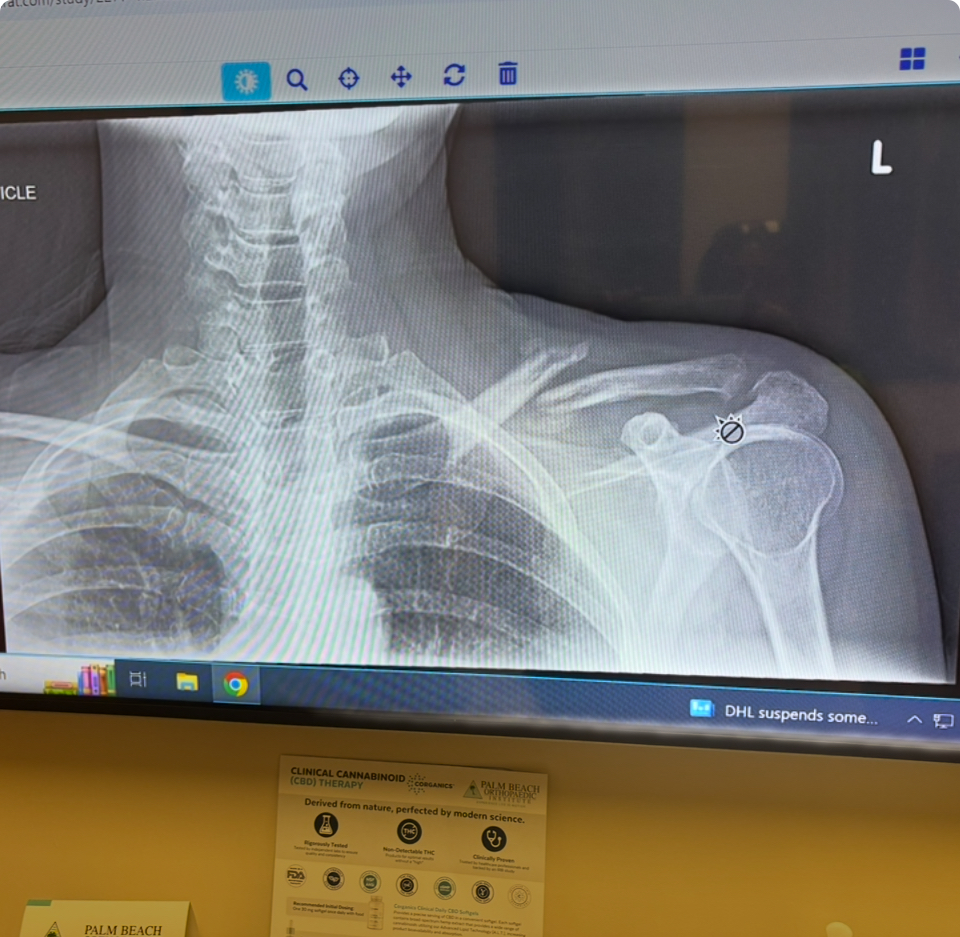

Hey friends and family, my name is April. I had a bad fall and broke my collarbone and kneecap. To try to avoid surgery, I'll be starting PT ASAP. I just started working again prior to the injury. I am asking for a little help to take some pressure off my sweetheart who has to carry me once again financially. Bills are piling up like crazy. Thank you kindly ❤️ I’ll be posting the pictures of the X-rays of my knee and shoulder very soon. My deductible is crushing us so I’ve opted to do PT at home for my knee. I’ll only have to go in for my shoulder. Thank you for your help, love and support!

thank you so much for your donations! I was able to get caught up with my health insurance and put some money towards the cc that I have maxed out using it for my doctor visits. I greatly appreciate your help. Please share my fundraiser with your friends and family. Any little amount helps greatly. I am so bummed to be out of work again. Staying positive and plugging along. Doctor said 6 weeks for my kneecap to heal. Shoulder Dr wants to see how I’m healing before we have to do surgery which would entail re breaking it, bone grafting along with a plate. After that heals , he would go back in to remove the plate. Praying I don’t have to go that route.

I saw the shoulder doctor today. Shoulder is slowly healing but I’m devastated as he said it will alway be messed up and slump down and forward. Also because of this and my knee , I feel again and have done something really back to my back. Having multiple severe spasms. I am going to see a spine specialist asap. Being in the car is super painful. Walking , but mostly sitting . Bummed. Thank you all for your support and kindness.